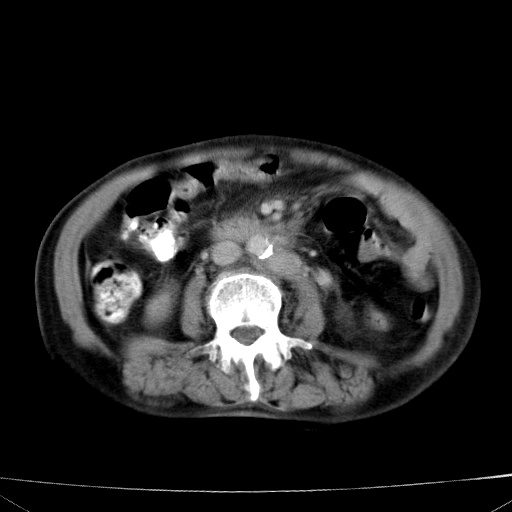

网站人气太旺!昨天的帖子就沉到海底,只好再发贴!ct18338:女 78岁,肝胆病变,已增强,再会诊!原帖链接:http://www.radida.com/bbs/forum.php?mod=viewthread&tid=50032

1)考虑胆囊癌侵犯肝脏并肝门区、腹膜后及右侧膈角后淋巴结转移。2)肝左叶近肝顶部囊肿。3)肝左叶肝内胆管结石。4)左肾近下极囊肿。